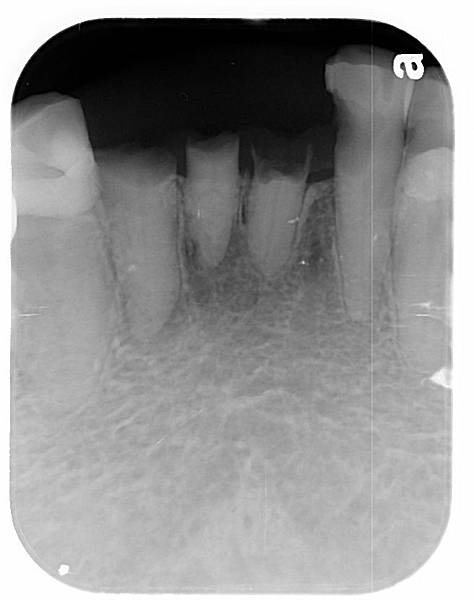

諮詢活動假牙的時候遇到拔牙的問題,病人常會有許多疑惑,最常見的尤其是:「這顆牙齒還很強壯為什麼要拔掉」。

這是一個很大也很複雜的問題,隨著不同的治療方式、不同醫師之間都對同一顆牙齒的去留有不同的意見。我提供幾個參考的方向,但這也都不是絕對的答案,最終還是要在臨床上做最後的評估。